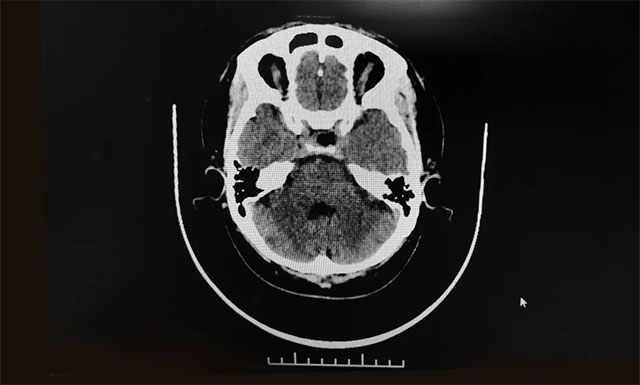

目前的影像学检查对早期确诊垂体瘤有重要意义,如怀疑为垂体瘤,通常经过正规医院的磁共振检查和CT 扫描,就可以及时把垂体瘤这个“元凶”揪出来。

随后,患者进行了头部鞍区MRI平扫+增强,结果显示:蝶窦显著扩大,鞍区见一类圆形肿块,大小约2.0*1.5*1.3cm。垂体柄缩短、左侧偏移;病变向鞍上生长,占据鞍上池,推移视交叉;向下生长,鞍底受压变薄;向鞍旁生长、紧贴海绵窦。

▲ 术后影像显示肿瘤被切除